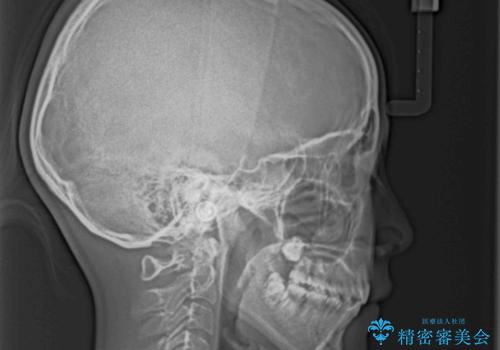

- 口元の突出感で口が閉じにくいとのことで来院された患者様です。

上下左右の第一小臼歯4本を抜歯し、ワイヤー装置での抜歯矯正を行うこととしました。

右側の咬み合わせは、上顎がやや前方位にある状態であったので、通常は補助装置を併用するのですが、高校生ということで補助装置なしで治療を行うこととしました。

口元の突出感が解消され、睡眠時の口呼吸が改善されました。